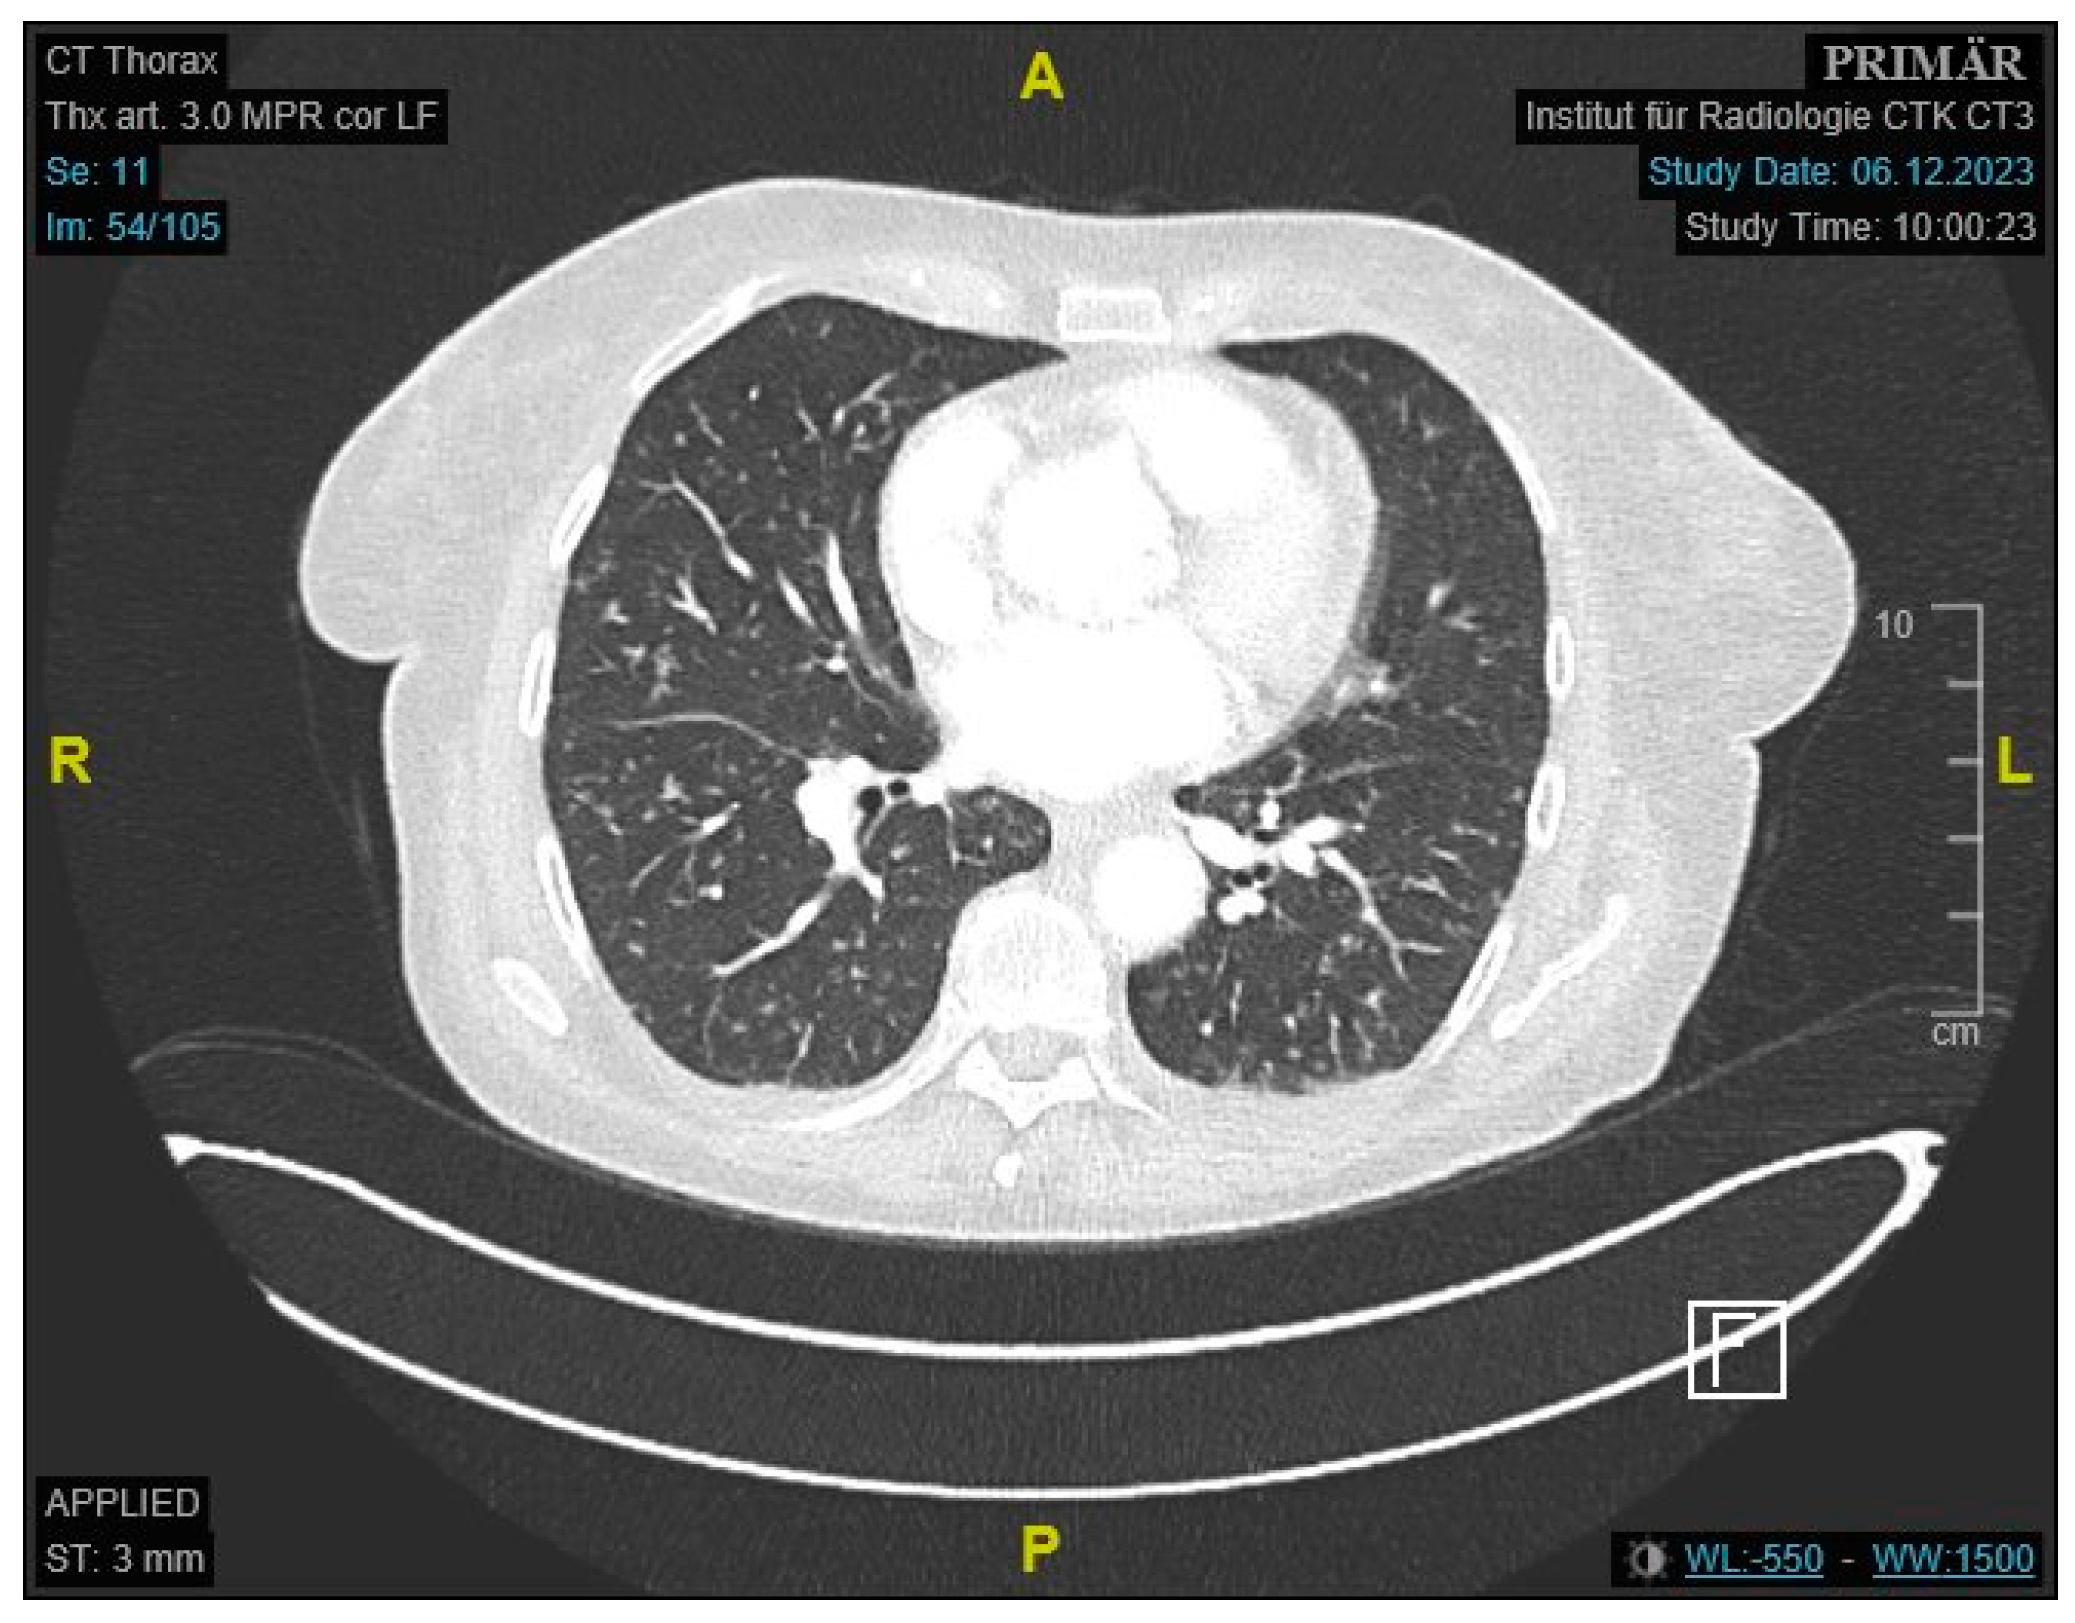

Initial labs showed microcytic anemia with suspicion of iron deficiency. Abdominal ultrasound showed marked ascites and findings suggestive of peritoneal carcinomatosis. A CT of the abdomen revealed a small bowel conglomerate tumor (Figure 1) and enlarged paraaortic lymph nodes. Chest CT demonstrated bilateral scattered consolidations suspicious for metastatic spread (Figure 2). Bronchoscopy was unremarkable, and direct microscopy was negative for AFB. Subsequently, the patient developed a small bowel ileus, raising suspicion for a jejunal tumor. During the subsequent emergent laparoscopy, we observed a conglomeration tumor consisting of the loops of the small intestine. Emergency laparoscopy revealed a small bowel conglomerate mass, and the biopsy from the lower abdomen showed caseating granulomatous peritonitis (Figure 3). A detailed history revealed her partner had previously been diagnosed with pulmonary tuberculosis caused by Mycobacterium chimaera. The patient had no follow-up for TB because her partner was considered not infectious.

Figure 1. Contrast-enhanced CT of the abdomen showing an approximately 4.1 cm mass, consistent with a small bowel conglomerate tumor.